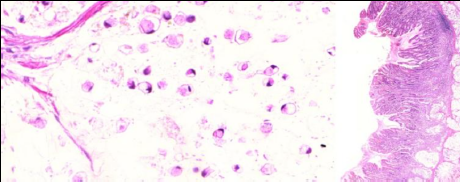

3. Adenocarcinoma pouco coesivo (A533)

1. Células em anel de cinete mergulhadas em lagos de mucina